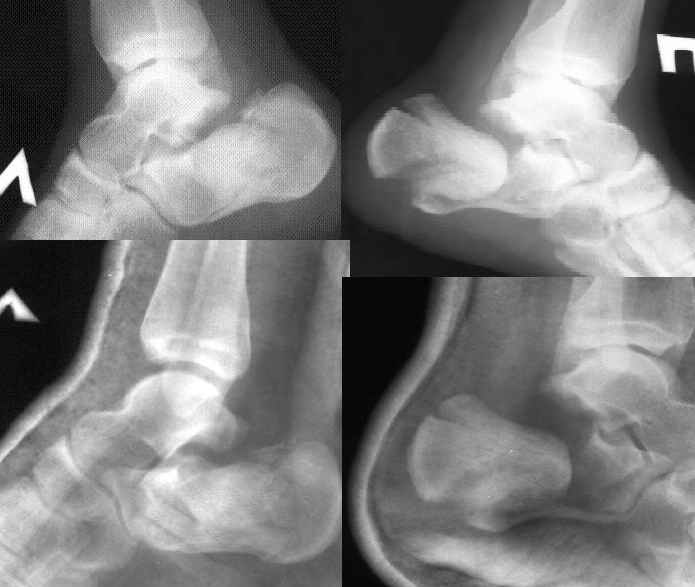

Уважаеемый коллега.Слева ситуация достаточно не сложная.Суставной фрагмент вклинился в тело.Необходимо наружным доступом освободить отломки,поднять суставной фрагмент и фиксировать пяточной пластиной LCP.

Спасибо! Но... В данном случае имеет место значительная компрессия тела пяточой кости (с обеих сторон, разумеется). Я мыслю, что необходима костная пластика. И ещё, - напрочь отсутствуют пластины для остеосинтеза пяточных костей. Возможно ли применить обычные реконструктивные пластины, или, на худой конец, спицы?

Справа ситуация сложнее так как имеется помимо перелома имеется вывих тела пяточной костиПоэтому даже если удастся достигнуть хорошей репозиции необходимо сделать первичный подтаранный артродез.Иначе кость не будет держать в своём ложе.Но пластина нужна обязательно чтобы восстановить форму пятки.С уважением Дрягин

Otkritaya repositsija, fixatija plastinoj. Sprava podtaranniy artrodez.